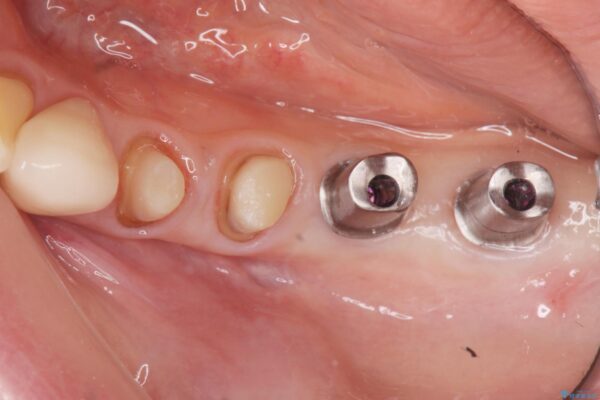

治療前

劣化の進んだブリッジの再治療[ 不適合な補綴物による虫歯の再発 ] 治療前画像 劣化の進んだブリッジの再治療[ 不適合な補綴物による虫歯の再発 ] 治療前画像 劣化の進んだブリッジの再治療[ 不適合な補綴物による虫歯の再発 ] 治療前画像